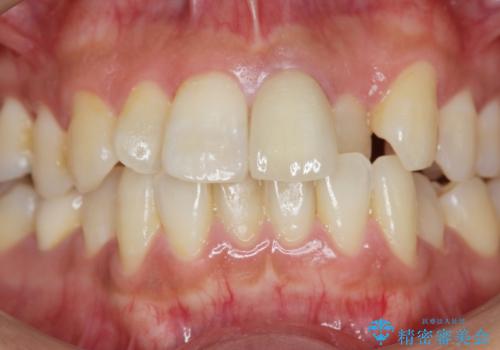

- 前歯の変色の改善を求めて来院されました。

前歯は虫歯などにより神経治療がよく行われますが、経年的に変色が進み審美性が損なわれていきます。